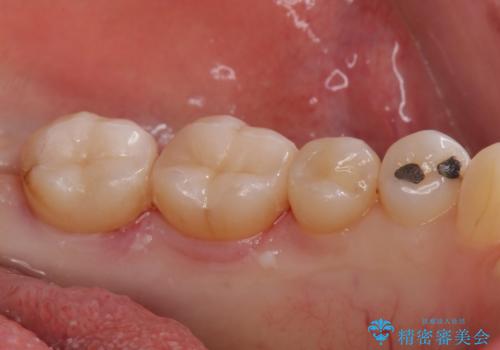

アマルガムを除去 虫歯を除去して、セラミックのつめものに

②2回目 製作したセラミックインレーの接着

- 左下6番、左下7番 セラミックインレー 7.7万円×2本費用は治療当時の料金となります